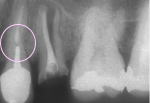

- グラスファイバーの弾性により、歯への負担を大幅に軽減

- 弾性係数が最も象牙質に近似しているため、歯に応力が加わった場合、歯のたわみに応じて屈曲し応力開放を助けます。

- メタルコアは硬すぎるために、歯根破折の原因となることがありますが、グラスファイバー系コアは適度なやわらかさがあり、歯根破折がたいへん少なくなります。